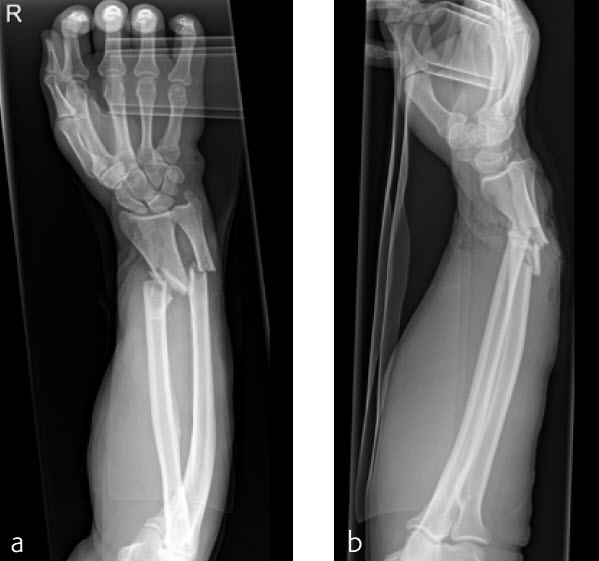

Case 4: Open radius shaft fracture

A 59-year-old farmer suffered a crush injury with an open forearm fracture (AO22 C2, Gustilo and Anderson IIIB) (Fig 1). Initial stabilization was carried out by external fixator (Fig 2). After four rounds of debridement and capillary ingrowth of a splitting skin graft at day 17, the VA LCP Extra Long Two-Column plate was used for fixation of the radius. A 2.7 mm LCP Condylar Plate was used for fixation of the ulna. The plates provided good stability for a functional after-treatment.